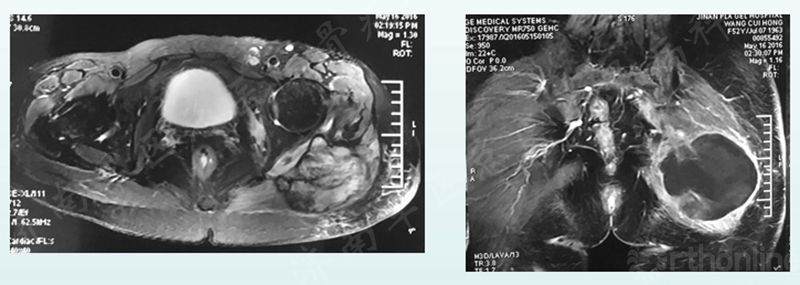

术后2个月,2016-3-17MRI检查示肿瘤复发,为寻求更好治疗,于2016-3-24入济南军区总医院骨病科。经多学科医生会诊后欲再行手术治疗,合并术前同步放化疗。2016-5-16放化疗后肿瘤边界变清晰,故行手术切除术。

术前同步放化疗前后对比

放化疗后肿瘤边界变清晰

放化疗前后效果对比